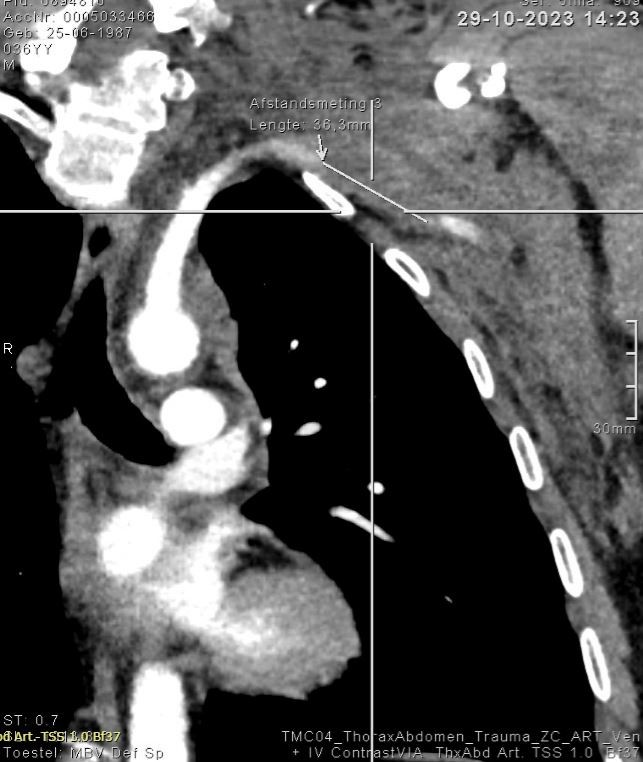

Figure 2: Computed tomography – scan of the left shoulder region without contrast:

Visualization of a non definable portion of the left subclavian artery with a length of 36 mm.

Figure 3: Computed tomography – angiography confirms the lesion of the left

subclavian artery.